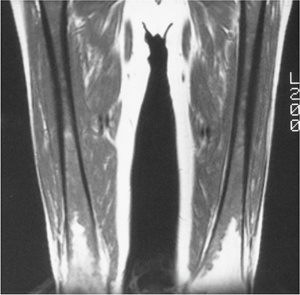

054fa6c227b9d394856ffc42110206ba.gif

图-2长跑运动员的骨髓增生。冠状位(A)和矢状位(B)的T1像显示股骨骨干和干骺端骨髓呈低信号,伴有胫骨处局灶性增生区。皮质骨正常,且无软组织异常。